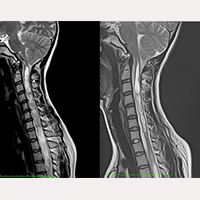

SFT po operacji odbarczenia

Według naszych badań, operacja Odbarczenia stosowana w przypadku Syndromu Arnolda Chiari I niweluje ucisk ktory istnieje w otworze potylicznym na poziomie struktur nerwowych, jednak nie eliminuje przyczyny napięcia całego systemu nerwowego czyli napięcia nici końcowej Filum Terminale dużo grubszej niż u osoby zdrowej. Z tego powodu stan pacjentow zoperowanych techniką Sekcji Filum Terminale u ktorych wcześniej przeprowadzono Odbarczenie poprawia się.